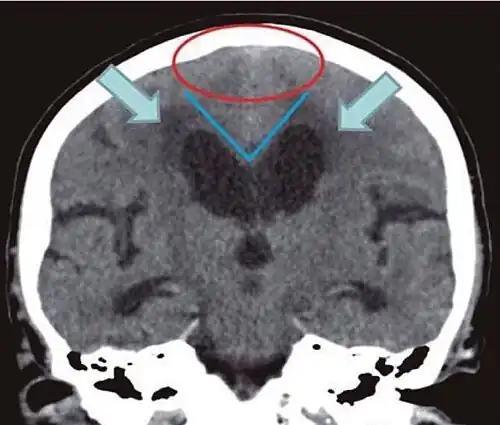

- Imaging from magnetic resonance imaging (MRI) or computed tomography (CT) is needed to demonstrate enlarged ventricles and no macroscopic obstruction to cerebrospinal fluid flow. Imaging should show an enlargement to at least one of the temporal horns of lateral ventricles, and impingement against the falx cerebri resulting in a callosal angle ≤ 90° on the coronal view, showing evidence of altered brain water content, or normal active flow (which is referred to as "flow void") at the cerebral aqueduct and fourth ventricle.

| Normal pressure hydrocephalus | Brain atrophy | |

|---|---|---|

| Preferable projection | Coronal plane at the level of the posterior commissure of the brain. | |

| Modality in this example | CT | MRI |

| CSF spaces over the convexity near the vertex (red ellipse |

Narrowed convexity ("tight convexity") as well as medial cisterns | Widened vertex (red arrow) and medial cisterns (green arrow) |

| Callosal angle (blue V) | Acute angle | Obtuse angle |

| Most likely cause of leucoaraiosis (periventricular signal alterations, blue arrows |

Transependymal cerebrospinal fluid diapedesis | Vascular encephalopathy, in this case suggested by unilateral occurrence |

MRI scans are the preferred imaging. The distinction between normal and enlarged ventricular size by cerebral atrophy is difficult to ascertain. Up to 80% of cases are unrecognized and untreated due to difficulty of diagnosis.[22] Imaging should also reveal the absence of any cerebral mass lesions or any signs of obstructions. Although all patients with NPH have enlarged ventricles, not all elderly patients with enlarged ventricles have primary NPH. Cerebral atrophy can cause enlarged ventricles, as well, and is referred to as hydrocephalus ex vacuo. For these reasons it's utmost important to note that Evan's index although commonly used in imaging is not very specific for NPH. One recent systematic review and meta-analysis suggests that callosal angle has high diagnostic performance and is commonly used together with Evan's index.[23]